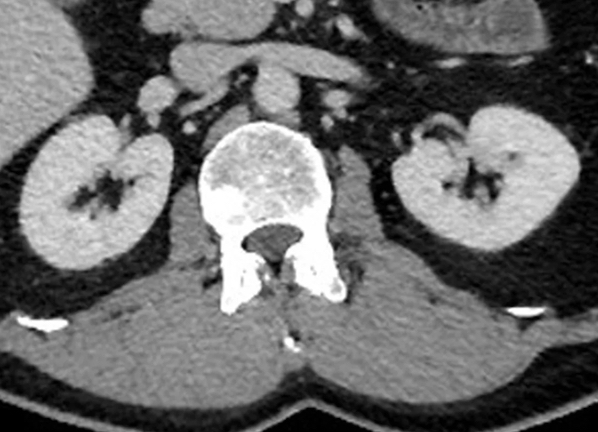

La maladie rénale chronique touche environ 37 millions d’adultes aux États-Unis, selon les Centers for Disease Control and Prevention. Une option de traitement pour l'insuffisance rénale avancée est l'hémodialyse, qui nécessite la création d’un accès à la circulation sanguine en installant soit une fistule ou une greffe artérioveineuse (AV).

Alors que les fistules AV sont la méthode préférée pour l'accès à la dialyse, certains patients peuvent avoir besoin d’une greffe AV lorsque leurs veines sont trop petites ou trop faibles pour une fistule. « Les patients souffrant d'insuffisance rénale font souvent l’objet d’une greffe AV pour faciliter la dialyse, précise la co-auteure de d’une étude sur le sujet publiée dans la Revue Radiology, le Pr Hillary J. Mull, chercheuse au Center for Healthcare Organization and Implementation Research pour le VA Boston Healthcare System in Massachusetts (USA) et professeur agrégé de chirurgie. Ces greffes peuvent échouer avec le temps, nécessitant qu'un radiologue interventionnel réalise une procédure d'entretien. Si la procédure a une complication dans les 30 jours, le patient aura besoin d'une autre procédure immédiatement pour résoudre le problème ».

Dans cette étude de cohorte rétrospective, compilant les données médicales de la Veterans Health Association (VHA), les chercheurs ont identifié 1 950 procédures de greffe AV chez 995 patients (principalement des hommes) dans 61 établissements VHA. L'âge moyen des patients était de 69 ans. La plupart des procédures (60 %) impliquaient des patients afro-américains et des patients résidant dans la partie sud des États-Unis (51 %). La majorité des actes a été réalisée par des radiologues interventionnels. Des échecs prématurés de greffe sont survenus dans 11 % des procédures. Après avoir contrôlé divers facteurs, tels que les facteurs socio-économiques et les comorbidités, la race afro-américaine était plus souvent associée à un échec prématuré de la greffe.